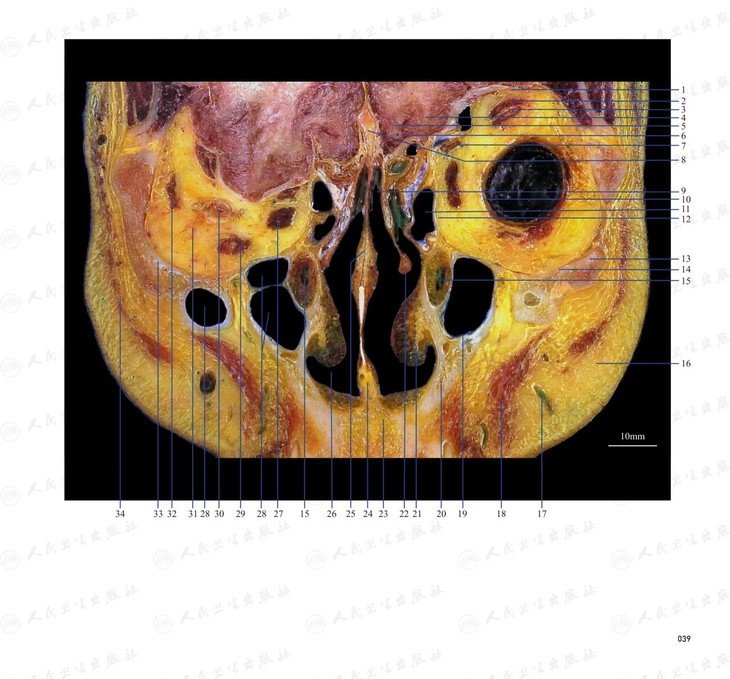

本书从数据集每隔1.2mm选取一幅图像,截取眼、耳、鼻及毗邻颅底的局部区域图像,共112幅图像。同时配以相应部位的CT图像对照。本书特色是断层解剖图利用数字图像处理技术优势,放大并清晰展示眼、耳、鼻及毗邻颅底断面的局部区域结构,组织色泽真实,甚至能够清晰显示肌肉纹理、筋膜纹路等细节结构,图像质量高于美国同类断层解剖彩色图的图像质量。对眼科、耳鼻咽喉科和神经内外科医生理解相关解剖结构有较大帮助。